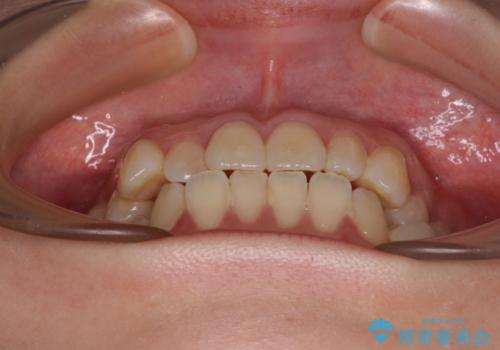

- 患者様は「歯並び全体のデコボコが気になり、人前で笑うことに抵抗がある」とのことでご来院されました。

診査の結果、上下顎ともに叢生が認められましたが、ワイヤー矯正・マウスピース矯正のいずれでも対応可能な症例でした。

歯列矯正にはさまざまな治療方法があり、ライフスタイルや性格、ご希望によって最適な選択肢は異なります。

「マウスピース矯正が合うのか分からない」「できるだけ早く治したい」などのお悩みがある方も、まずはお気軽にご相談ください。

一人ひとりに合った治療計画をご提案いたします。